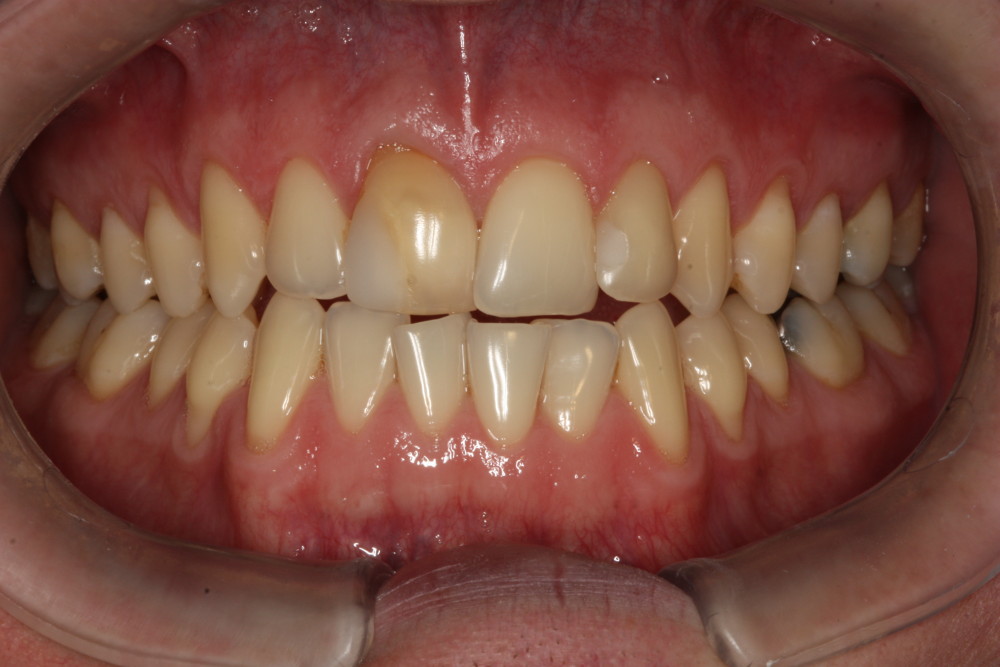

Przykład ekstruzji ortodontycznej za pomocą płytki termoformowalnej i zameczka ortodontycznego: